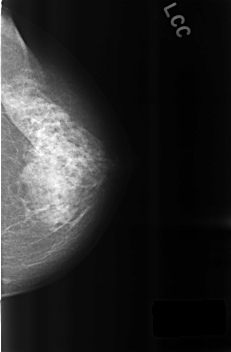

C_0315_1.LEFT_CC

LEFT_CC LINES 4568 PIXELS_PER_LINE 2992 BITS_PER_PIXEL 12 RESOLUTION 50 NON_OVERLAY